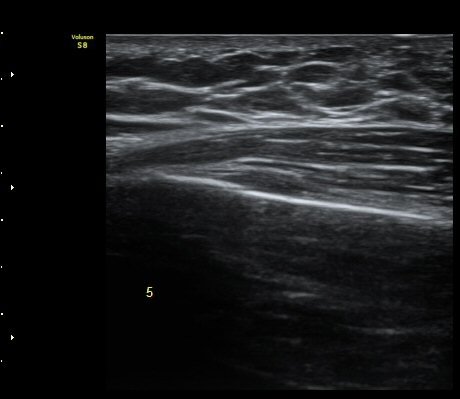

Á¾´Ü¸é°Ë»ç¿¡¼­ °¡°ñ Çü¼ºÀÌ °üÂûµÊ(formation of callus)   »çÁø 3

°¥ºñ»À Ⱦ´Ü¸é°Ë»ç¿¡¼­ °¡°ñ Çü¼ºÀÌ °üÂûµÊ(formation of callus)  »çÁø 4